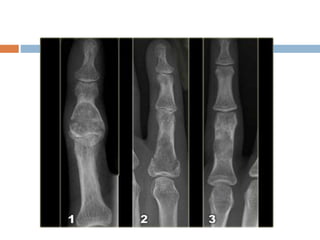

Chondroma

 Benign lesions of hyaling cartilage

 Any bone can be involved but mainly affects

phalanges of the hands and feet

Diagnosis

 Radiography

 Benign appearing tumors

 Translucent

 Intralesional calcification– irregular

(stippled/punctate/popcorn)

 Small bones of hand hands and feet–

considerable erosion and expansion of the

overlying cortex